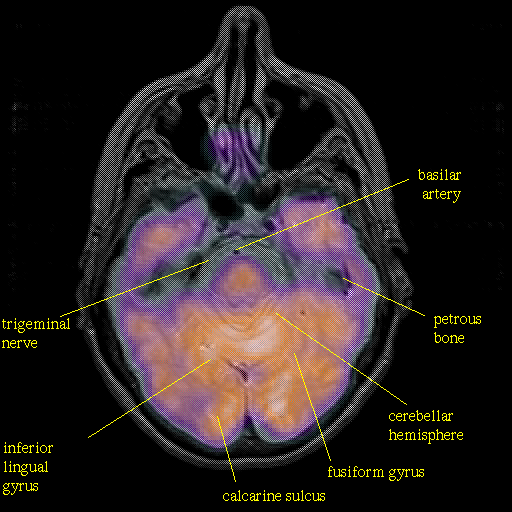

overlay : Slice 17

Slice 17

Pointers

Labeled